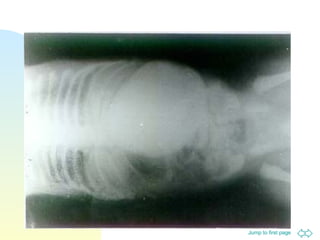

6 month old infant

Jump to firstpage 6 month old infant